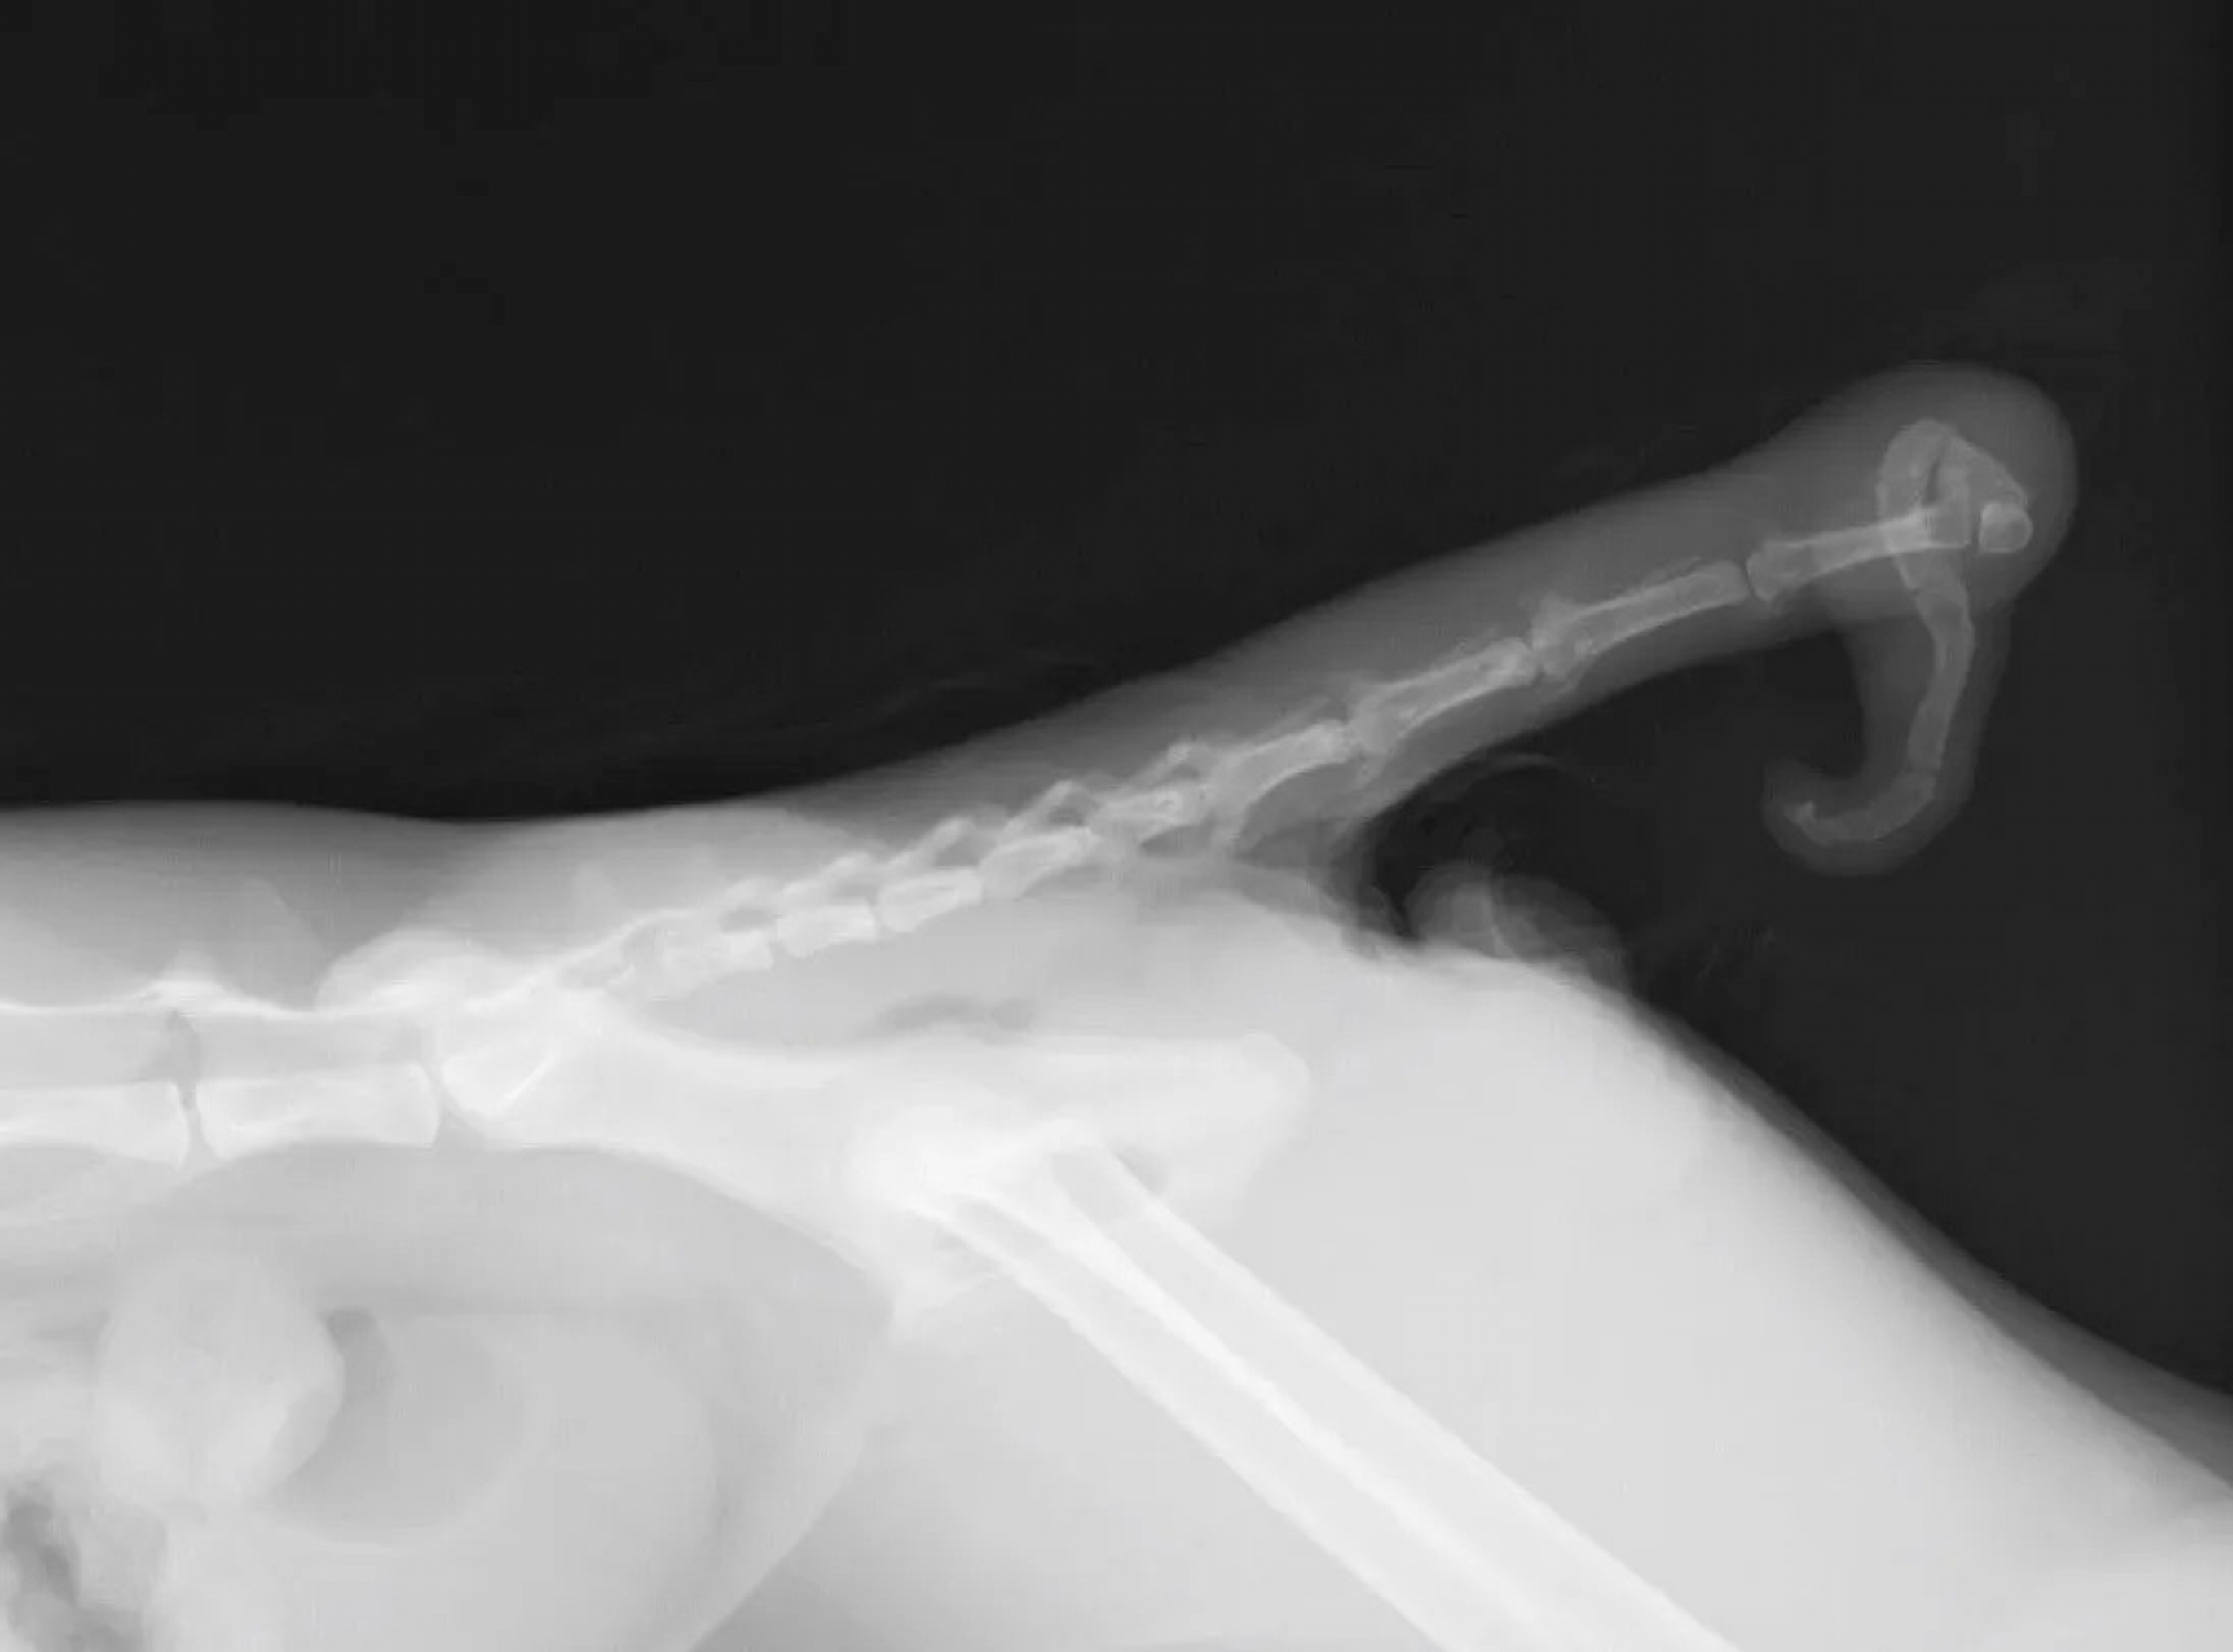

Οι ουρές τους έχουν λογής σχήματα. Είναι καμπυλωτές, σε σχήμα «γάντζου» ή σαν πιασμένος κότσος, εξηγεί ο Καζούγια Χιντεσίμα, εργαζόμενος στο Omagari Neko Shrine και μέλος του Nagasaki Cat Society.